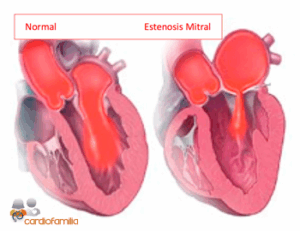

A principal causa de estenose mitral é a doença cardíaca reumática. Devido à estenose mitral, a sobrecarga...